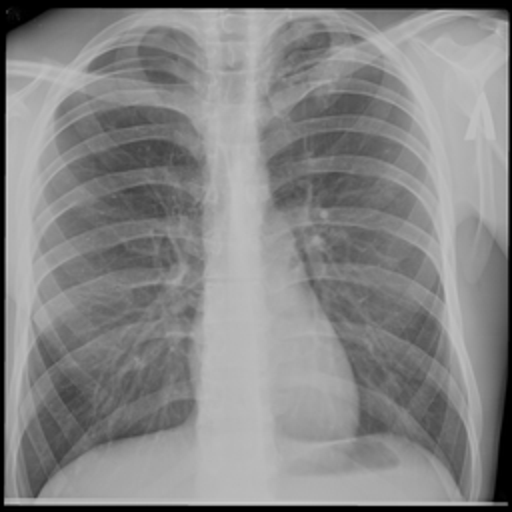

Moderate risk X-ray

Moderate Risk TB Prob: 61.3%

Subtle Lesion Detection

Female, 28y • Mild cough, routine screening

Faint nodular opacity in the mid-zone. Tests AI sensitivity to early-stage disease. Model: 61.3% TB probability.

Early StageNodule